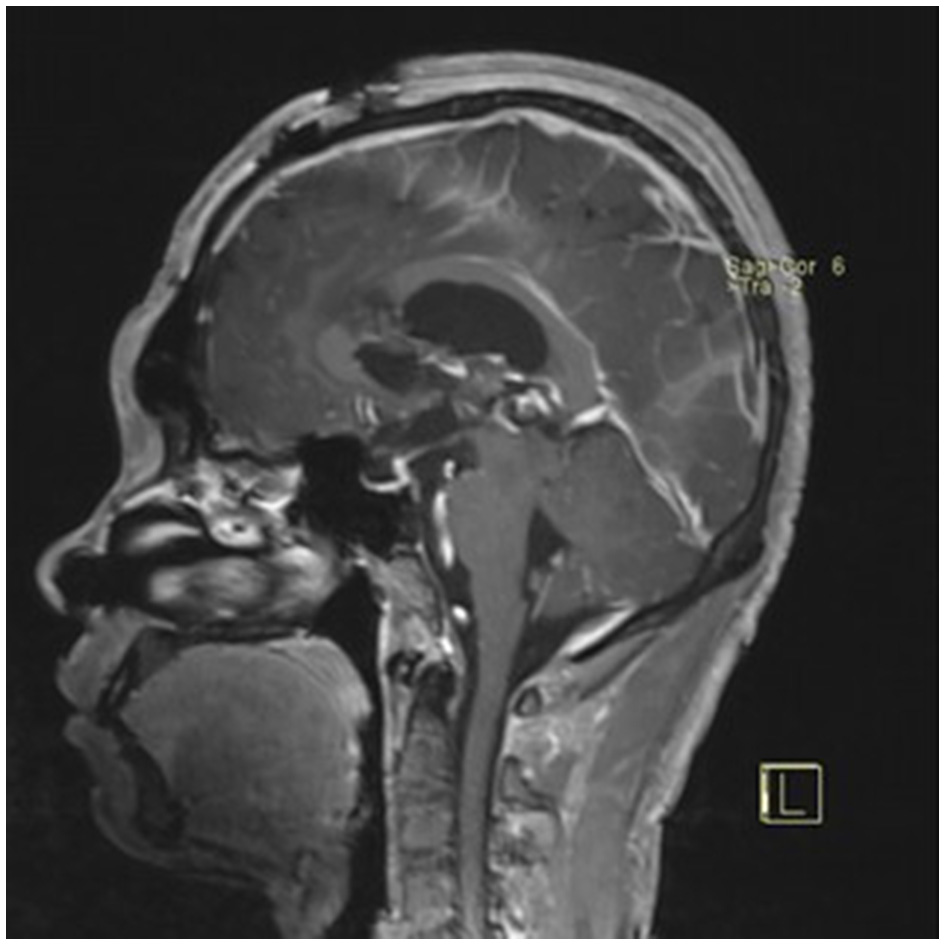

A 22-year-old male presented with intermittent dizziness and headache lasting for 2 weeks. MRI at admission revealed a cystic mass in the pineal region, accompanied by supratentorial hydrocephalus (Figures 3–5). No surgical contraindications were identified. After discussion with the patient's family, neuroendoscopic resection was performed via the Transfrontal-Transventricular-Transforaminal Approach. Intraoperatively, a 20 × 20 mm soft, well-vascularized tumor was found obstructing the cerebral aqueduct. The lesion had well-defined margins and was carefully dissected from surrounding adhesions, preserving adjacent veins and brain tissue. Macroscopic total resection was achieved en bloc (Figures 6–8). Postoperative day 1 MRI confirmed complete tumor removal and resolution of hydrocephalus (Figures 9–11). Postoperatively, no complications were observed. However, due to personal reasons, the patient was discharged on postoperative day 11. Histopathology confirmed a mixed germinoma. No recurrence or surgery-related complications were noted during follow-up.

Preoperative contrast-enhanced MRI (sagittal view) showing the pineal region tumor.

Figure 5

Preoperative contrast-enhanced MRI (coronal view) showing the pineal region tumor.